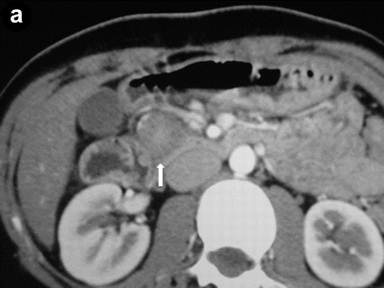

Patient#4: Focal form of autoimmune pancreatitis.

A 21-year-old woman presented with abdominal pain and a sonographic finding of a dilated main pancreatic duct in both the body and the tail sections. Axial images of the contrast-enhanced CT scan (arterial phase) (Image 4a) showed an enlarged pancreatic head with a hypodense lesion (arrow). Radial scanning EUS (Image 4b) confirmed a hypoechoic focal lesion of the pancreatic head (arrows) with an upstream dilatation of the common bile duct; the choledochal wall showed thickening with a "sandwich-pattern" (arrowheads). IgG4 levels were elevated.